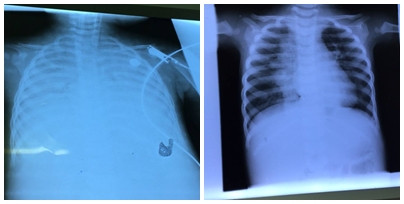

| Phim chụp phổi cháu bé trước (hình trái) và sau khi điều trị bằng kỹ thuật ECMO (hình phải). |